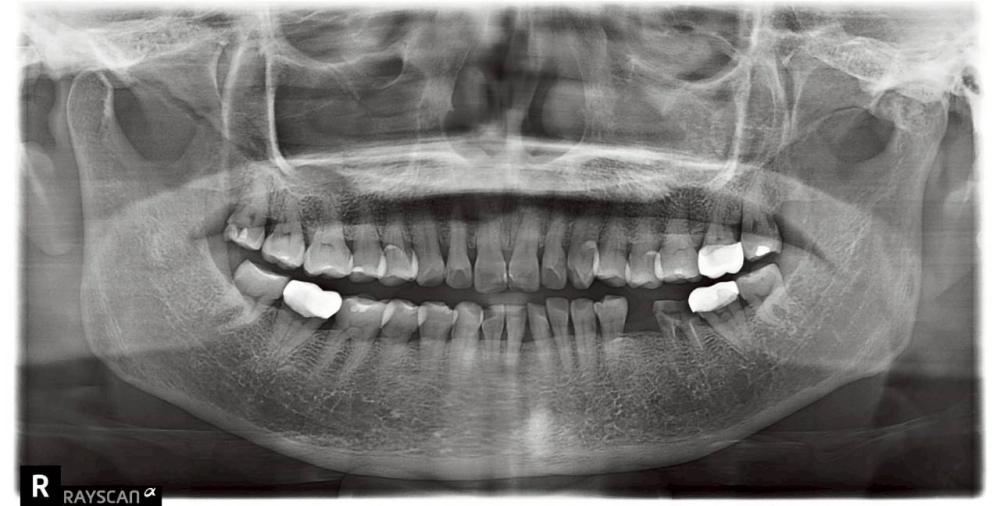

患者因左下後牙缺失(圖一),導致進食時長期依賴單側咀嚼。長期偏側咬合不僅造成肌肉負擔,更潛藏著鄰牙位移與對咬牙過度生長的風險。